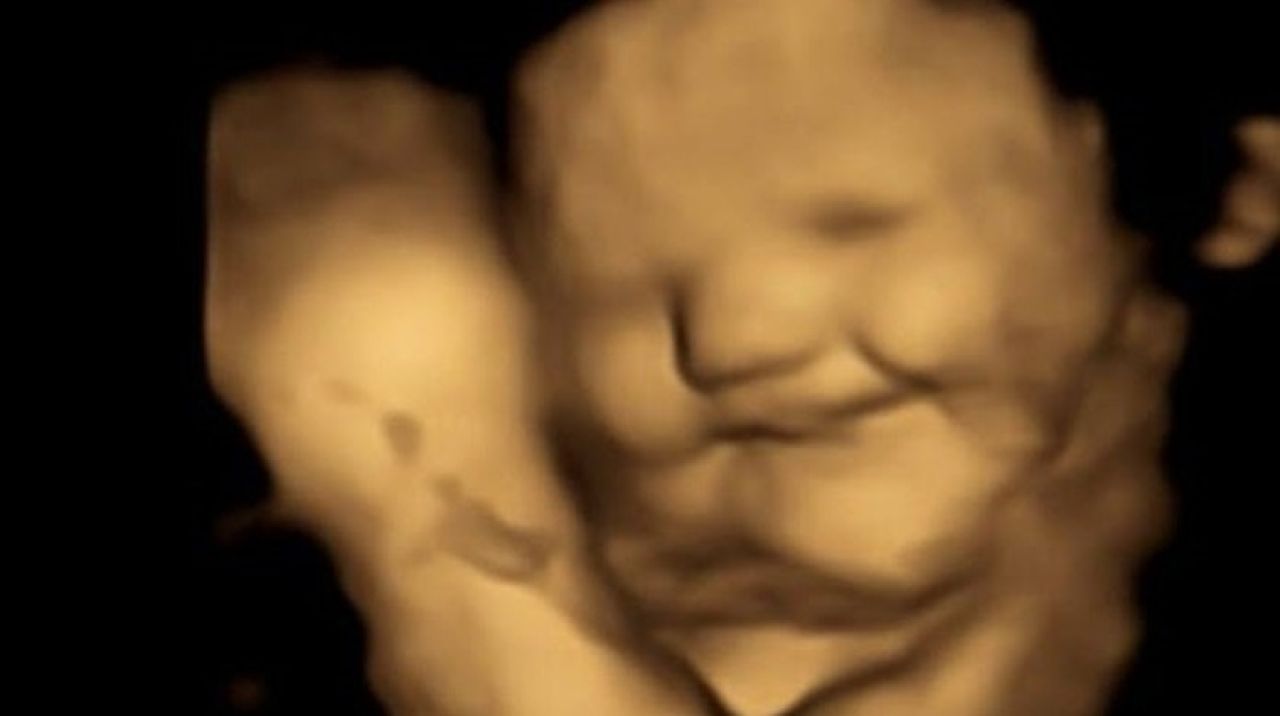

u003cbu003eANNE KARNINDAKİ BEBEKLER ANNELERİ HAVUÇ YİYİNCE GÜLÜMSÜYORu003c/bu003eYeni bir araştırma, bebeklerin daha anne karnındayken farklı tatlara tepki vermeye başladığını gösterdi. Durham Üniversitesi'nden araştırmacılar, 100 hamile kadın üzerinde yaptıkları çalışmada, dört boyutlu ultrasonla anneleri sebze yediğinde bebeklerin verdikleri tepkileri ölçtü. Sonuç dikkat çekiciydi!

Bebekler, anneleri havuç yedikten kısa süre sonra gülümserken, anneleri lahanayı tercih ettiğinde yüzlerini buruşturdu. Bulgular, hamile kadınların yediklerinin doğumdan sonra bebeklerinin tat tercihlerini etkileyebileceğini gösteriyor. Araştırmacılara göre, sonuçların sağlıklı beslenme alışkanlıkları oluşturmada etkileri olabilir.